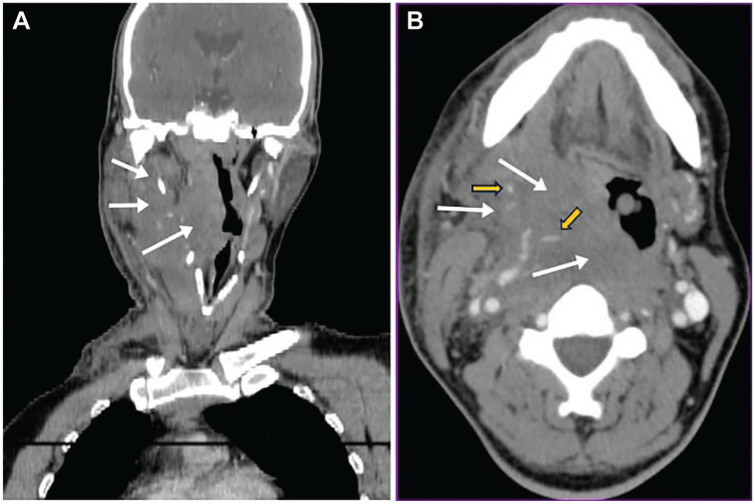

Case presentation: A 60-year-old man presented to the emergency with acute dysphagia, dysphonia and a right-sided neck ecchymosis. The patient had been on vitamin K antagonists for 7 years following a left intraventricular thrombus. Blood tests revealed an International Normalized Ratio of 7. The diagnosis of Spontaneous Retropharyngeal Hematoma was suspected given the absence of an identified cause and was confirmed by contrast-enhanced computed tomography. The hematoma was attributed to the patient's long-term use of vitamin K antagonists, which predisposed him to spontaneous bleeding. Treatment involved the administration of vitamin K but the patient ultimately passed as a result of respiratory arrest.